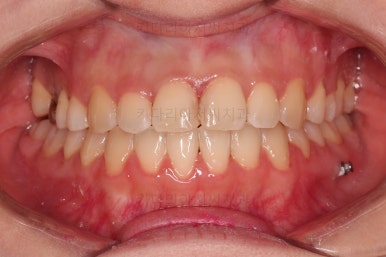

전후 비교 해볼게요.

가지런한 느낌, 교합, 중앙선, 반대교합 등 모든 면에서 개선이 되었고요.

얼굴 모습에서는 아랫니가 뒤로 들어감에 따라 웃는 모습도 윗니 위주로 보이면서 웃는 모습도 매우 좋아졌네요.

비대칭 부분은 뼈의 위치는 바뀌진 않았지만 교합을 바로 해줌으로 인해서 개선된 효과를 주고 턱관절 등 기능적으로도 개선이 되게 됩니다.